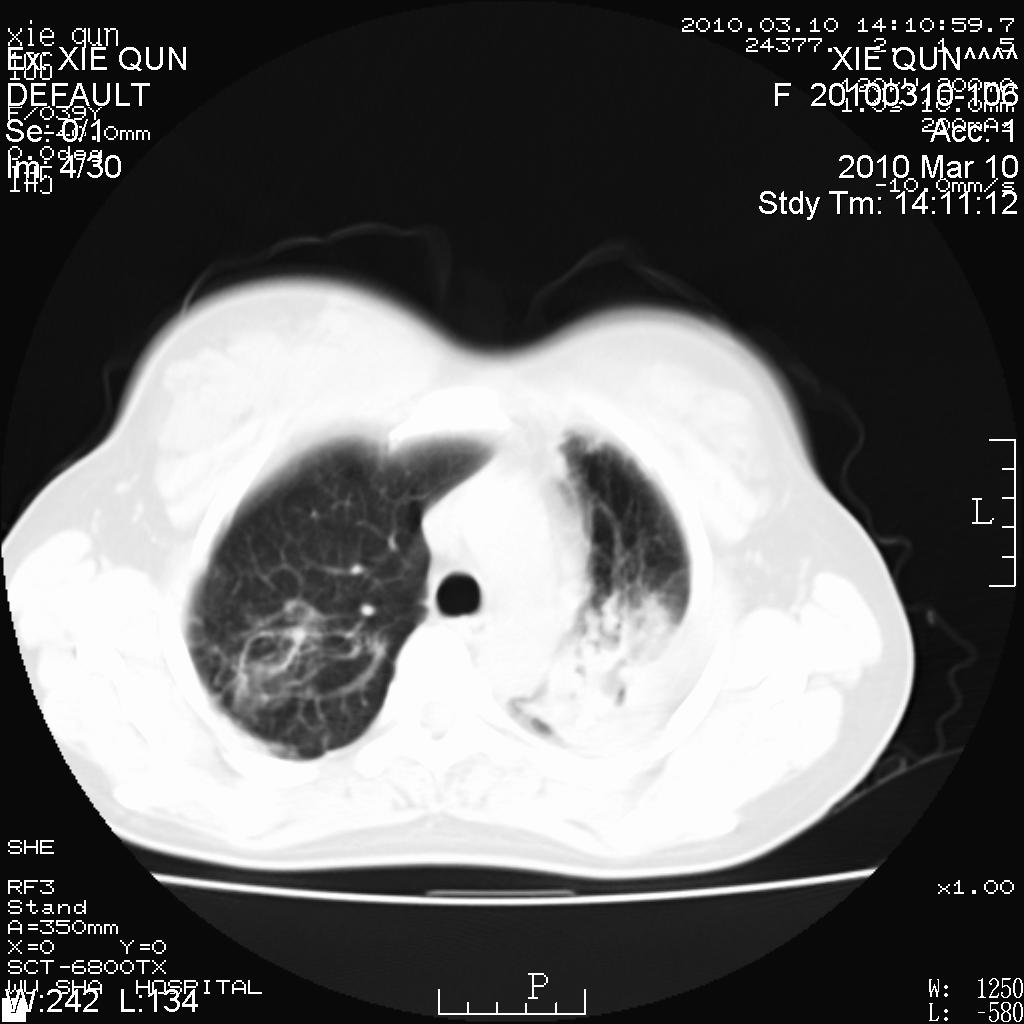

以下是引用心路寻觅在2010-3-24 17:28:00的发言:[br]两肺继发性tb左上肺空洞形成,建议痰检明确诊断。

以下是引用随光逐影在2010-3-24 19:19:00的发言:[br]两肺继发性结核并左上肺上叶空洞形成。